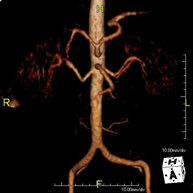

Prova diagnòstica no invasiva que consisteix en l'obtenció d'imatges d'alta definició anatòmica de tot el cos mitjançant l'ús d'un camp electromagnètic i ones de ràdio (amb un emissor i un receptor). No utilitza radiació ionitzant. És una prova molt important en la recerca de metàstasi en pacients amb neoplàsia coneguda. No requereix preparació prèvia. No és necessari l'ús de contrast paramagnètic (Gadolini). - Angio RM d'Aorta-ilíaca

Prova diagnòstica no invasiva que consisteix en l'estudi de l'artèria aorta abdominal i de les artèries ilíaques, amb l'obtenció d'imatges d'alta definició anatòmica mitjançant l'ús d'un camp electromagnètic i ones de ràdio (amb un emissor i un receptor). És indispensable l'ús de contrast paramagnètic (Gadolini). No utilitza radiació ionitzant. La qualitat de les imatges permet realitzar reconstruccions en 2D i 3D. Aquesta prova està especialment indicada com a estudi prequirúrgic (mapa vascular) abans d'intervencions percutànies o quirúrgiques d'aorta abdominal i artèries ilíaques, per a l'estudi complementari en pacients amb isquèmia de membres inferiors, etc. - Angio RM Arterial d'extremitats inferiors

Prova diagnòstica no invasiva que consisteix en l'estudi de l'artèria aorta abdominal per obtenir imatges d'alta definició anatòmica mitjançant l'ús d'un camp electromagnètic i ones de ràdio (amb un emissor i un receptor). És indispensable l'ús de contrast intravenós paramagnètic (Gadolini). No obstant, no utilitza radiació ionitzant. La qualitat de les imatges permet realitzar reconstruccions en 2D i 3D. Està indicat en aquells pacients amb malaltia vascular (Aterosclerosi), per a l'estudi d'aneurismes, en estudis prequirúrgics de lesions adjacents a l'aorta abdominal com "mapa" vascular, etc. - Angio-RM Aorta ilíaca

Prova diagnòstica no invasiva que consisteix en l'estudi de l'artèria aorta abdominal per obtenir imatges d'alta definició anatòmica mitjançant l'ús d'un camp electromagnètic i ones de ràdio (amb un emissor i un receptor). És indispensable l'ús de contrast intravenós paramagnètic (Gadolini). No obstant, no utilitza radiació ionitzant. La qualitat de les imatges permet realitzar reconstruccions en 2D i 3D. Aquesta prova està especialment indicada com estudi prequirúrgic (mapa vascular) abans d'intervencions percutànies o quirúrgiques d'aorta abdominal, per a l'estudi complementari en pacients amb isquèmia de membres inferiors, etc. - Angio-RM d'Artèries renals